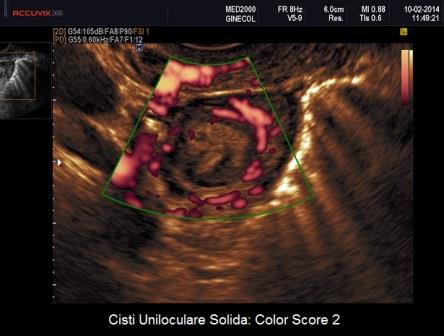

Per quanto riguarda le neoplasie abbiamo visto come il corpo luteo cistico può assumere l'aspetto di una Cisti Uniloculare Solida dove la componente solida è rappresentata dal coagulo endocistico. Un valido aiuto nella diagnosi differenziale ci è dato dal power-Doppler che ci consente di valutare le differenze di vascolarizzazione tra Cisti Luteinica e Cisti Uniloculare Solida di altra natura. La Cisti Luteinica ha una componente solida endocistica rappresentata dal coagulo che non è vascolarizzato al power-Doppler mentre presenta una parete riccamente vascolarizzata (ring of fire). Le Cisti Uniloculari Solide di altra natura possono avere una parete vascolarizzata ma non in maniera così intensa come per il corpo luteo ed hanno una componente solida (papille e parti solide) che può avere un Color Score variablie da 2 a 4.

A margine credo possa essere utile ricordare come si calcola il Color Score. Esso rappresenta una valutazione della vascolarizzazione di una neoformazione annessiale stimata soggettivamente dal medico ecografista secondo una scala che va da 1 a 4:

- Color Score 1: assenza di flusso

- Color Score 2: presenza di pochi spots vascolari

- Color Score 3: presenza di una discreta vascolarizzazione

- Color Score 4: presenza di abbondante vascolarizzazione